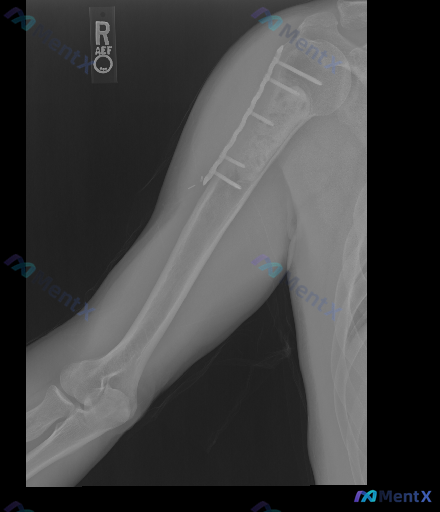

整理到一张右上臂肱骨正位X光片的术后随访资料,给大家分享一下读片所见并讨论: 基本背景:右侧肱骨近端至中段骨折内固定术后(具体术后时长未提供)。 影像学主要表现: 1. 右侧肱骨近端至中段可见接骨板及多枚螺钉存留;肱骨大结节区域也有内固定螺钉 2. 接骨板覆盖的肱骨干区域,可见骨质连续性中断,断端边...